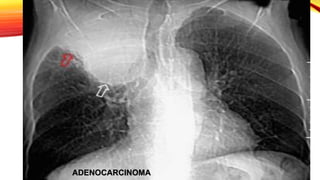

ADENOCARCINOMA

35-50% de CA de pulmón

Su incidencia es similar en

hombres que en mujeres

Suelen desarrollarse en la

periferia del pulmón

• Se presenta como nódulo o masa de distribución

periférica y ocasional presencia de broncrograma aéreo.

Atelectasia